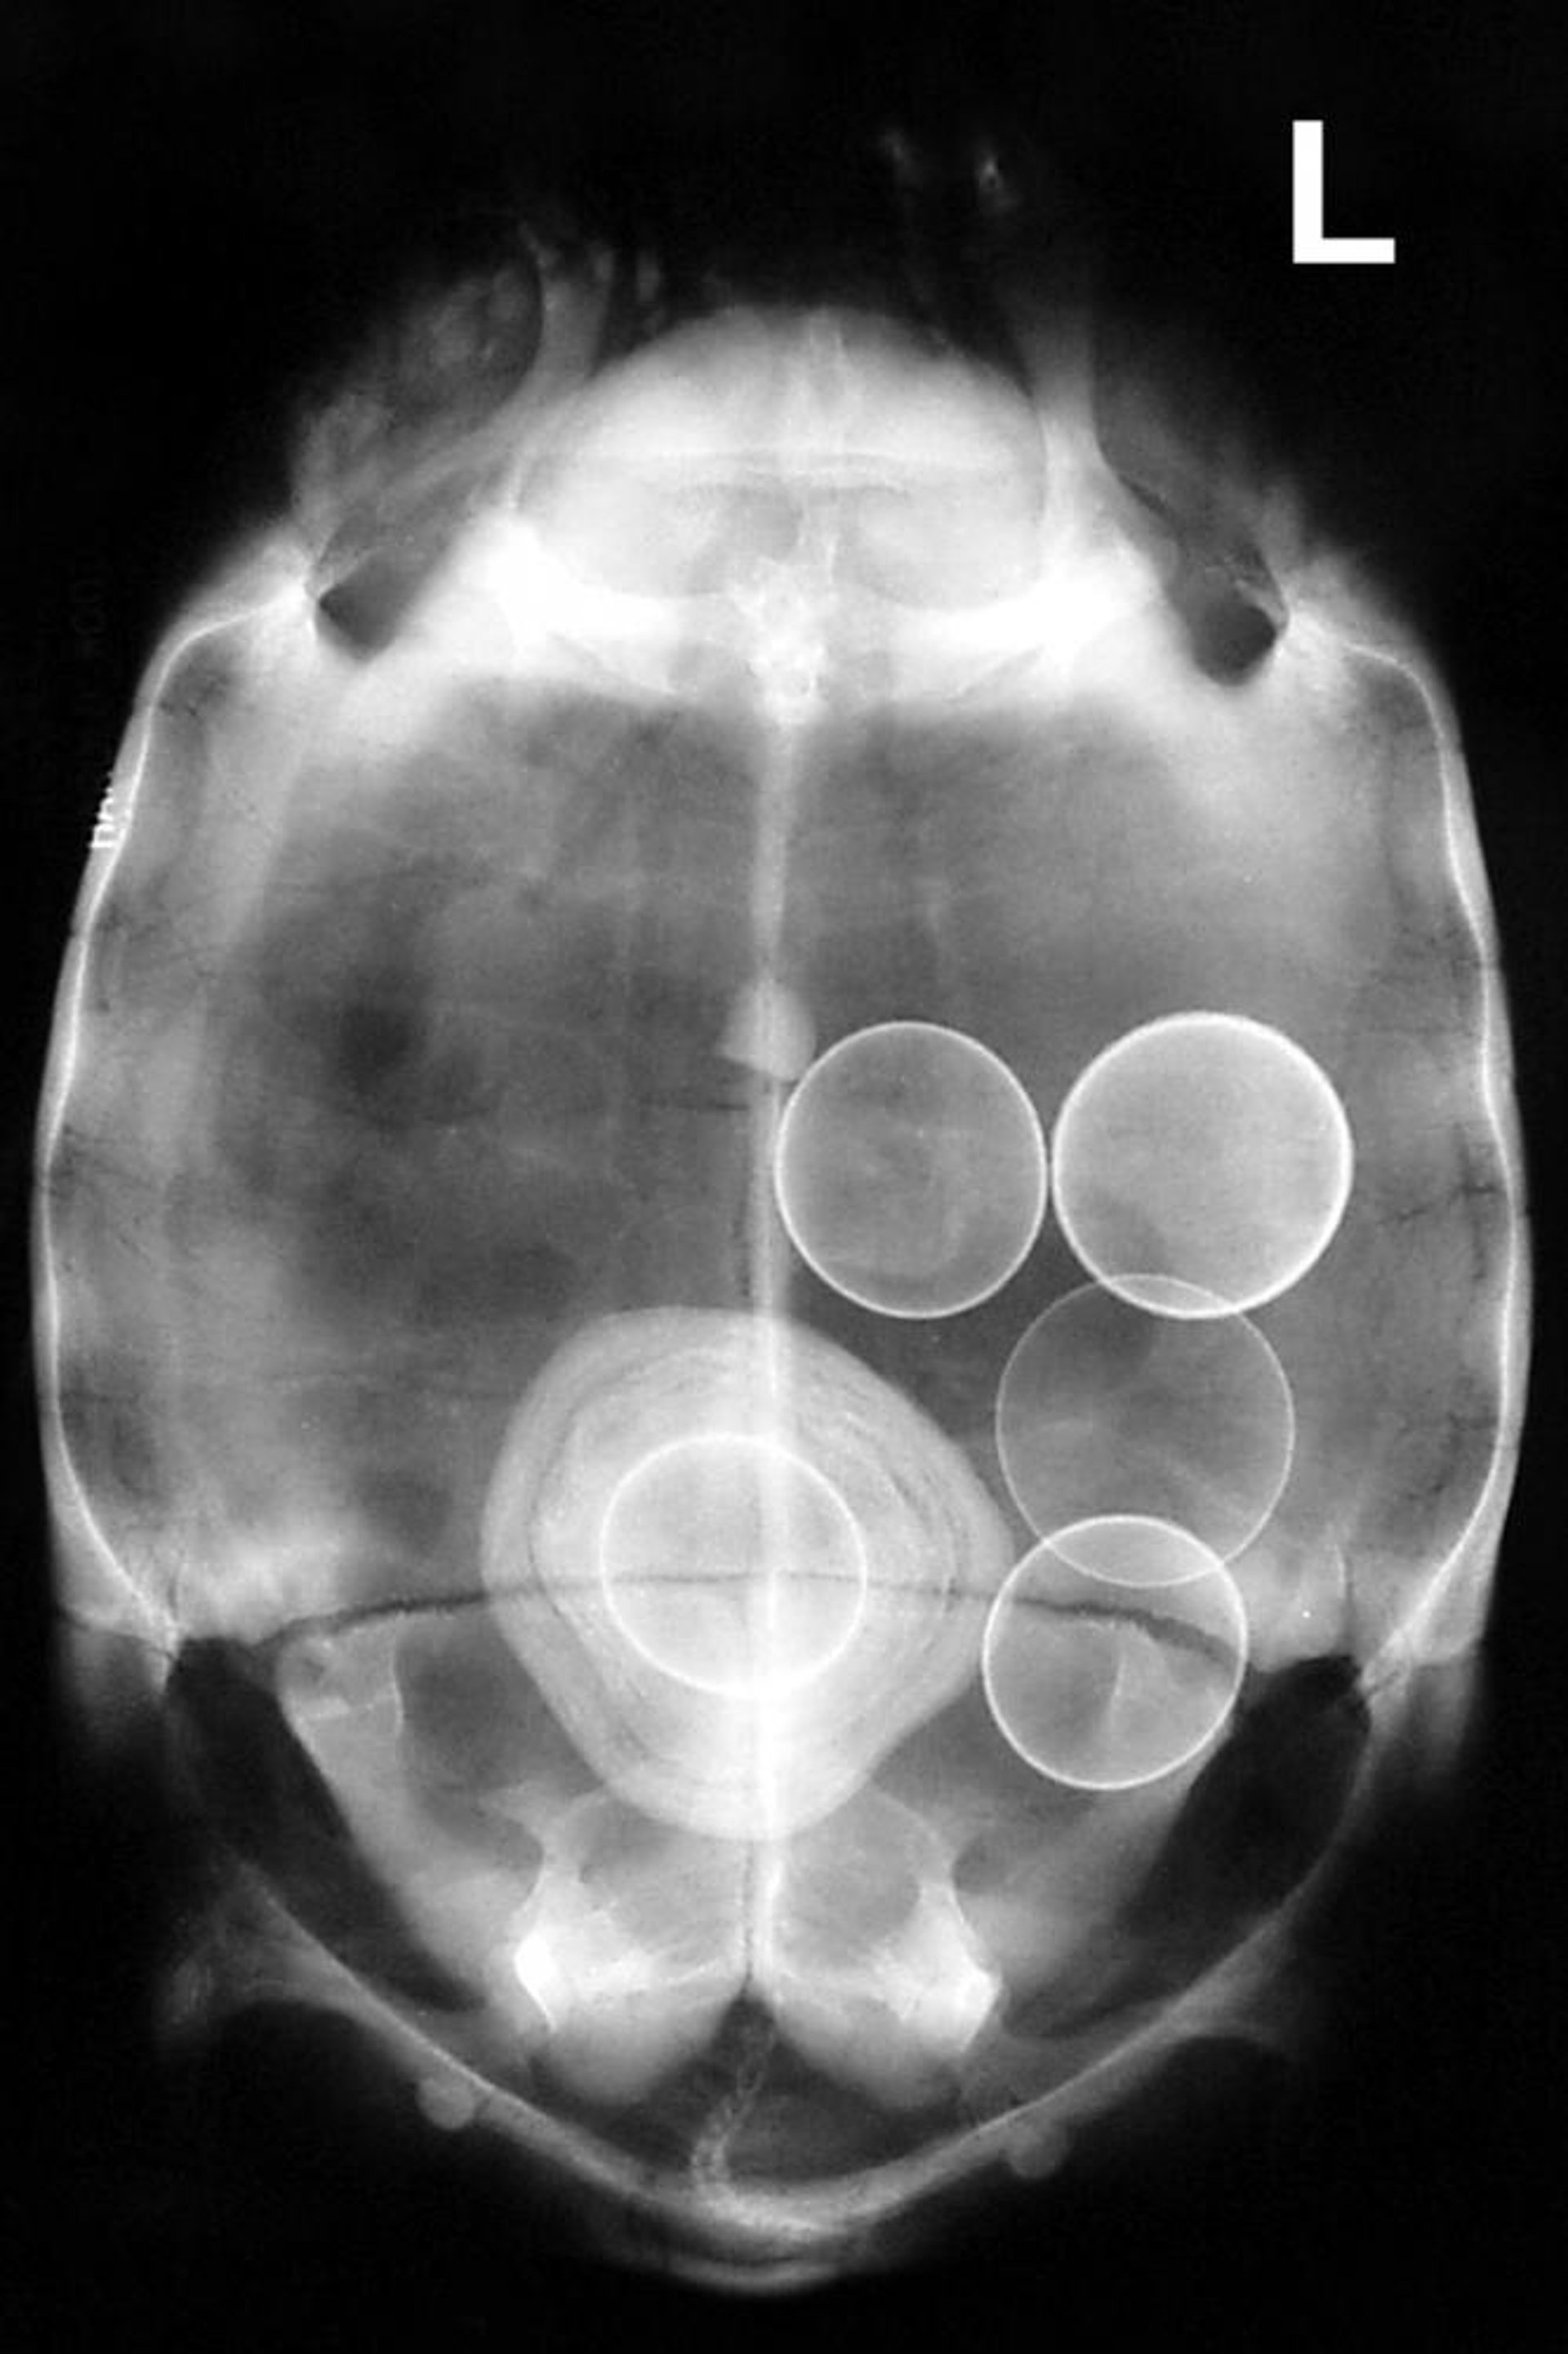

Chelonian, radiograph, dorsoventral view

Dorsoventral radiograph of a Greek tortoise (Testudo graeca) demonstrating several abnormal eggs, including one within the bladder and encased by uric acid, forming a large urolith.

Courtesy of Dr. Stephen Divers.